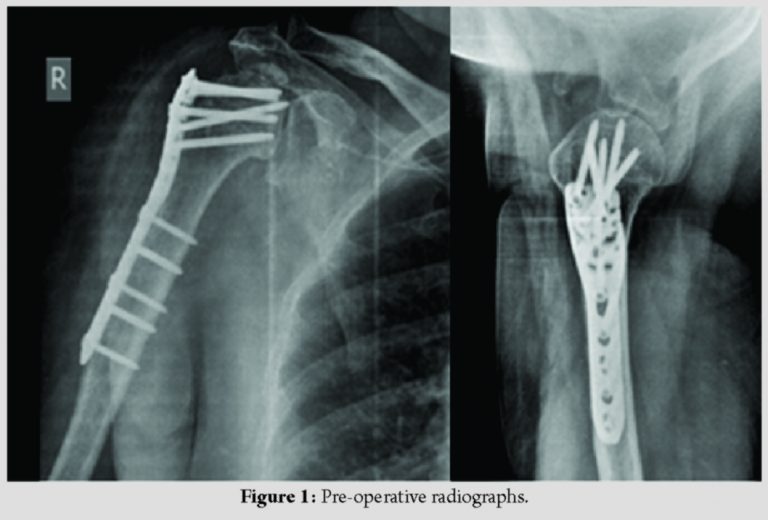

A 58-year-old female has sustained bilateral PHF in February 2018 due to electrocution. She was treated with ORIF with locking plate of both proximal humeri in a single stage. At 4-month follow-up, the left side fracture has united but on the right side, there was non-union with collapse of head and penetration of screw (Fig. 1). The patient is symptomatic with pain and inability to lift her right shoulder. The patient was advised computed tomography(CT) scan with 3D reconstruction of the right shoulder and nerve conduction studies to assess the deltoid function. After pre-operative evaluation, the patient was planned for reverse shoulder arthroplasty.